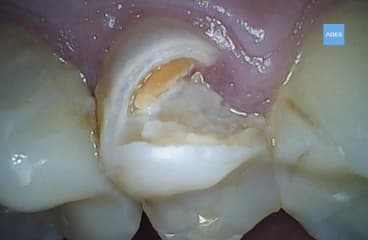

- Eliminar la pulpa infectada o dañada.

- Limpiar y desinfectar el conducto radicular.

- Sellar el conducto para evitar que las bacterias vuelvan a ingresar.